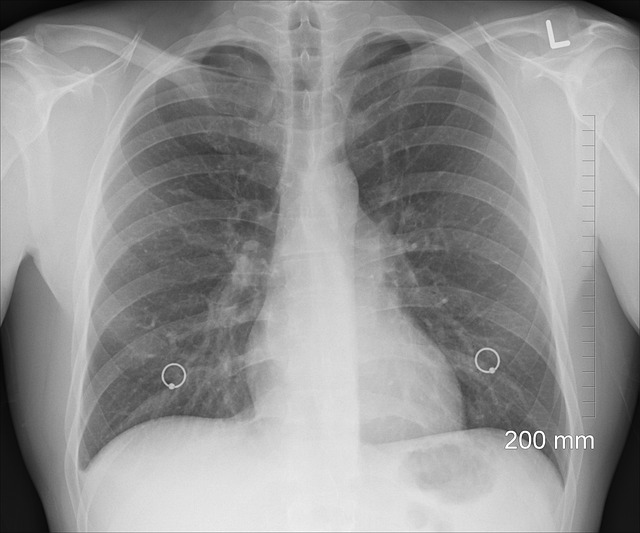

| 흉부 X-ray | 폐질환, 폐암 등 확인 | 매년 |